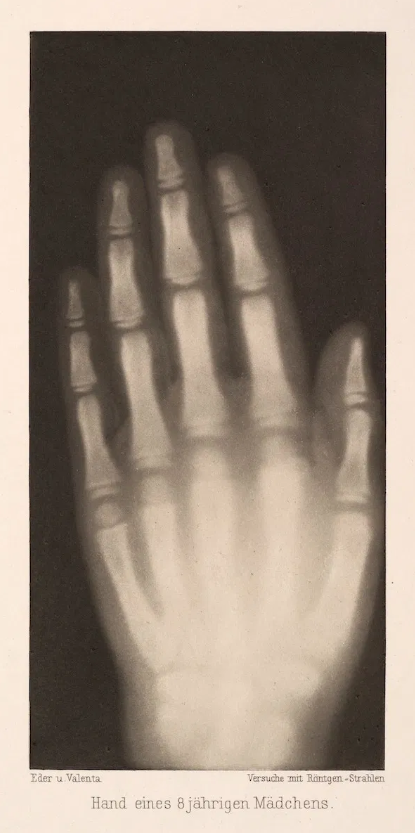

Такие попытки тоже были. Вот один из первых примеров фото-проекта 1896 года, подготовленного автсрийцами Йозефом Марией Эдером (1855–1944), директором института графических процессов, и Эдуардом Валентой (1857–1937), фотохимиком. Их портфолио под названием “Эксперименты по фотографии с помощью рентгеновских лучей” (Versuche über Photographie mittelst der Röntgen’schen Strahlen), содержало 15 изображений: смесь позитивов и негативов, включая, помимо скелетных форм животных и человеческих конечностей, рентгеновские снимки резных камео и различных материалов, таких как металл, дерево, стекло и мясо.

Согласитесь, что эти изображения довольно интересно смотреть и сегодня. Представьте, какое изумление они вызвали, когда были впервые опубликованы – а это произошло всего через несколько недель, как Рентген обнародовал свое открытие.